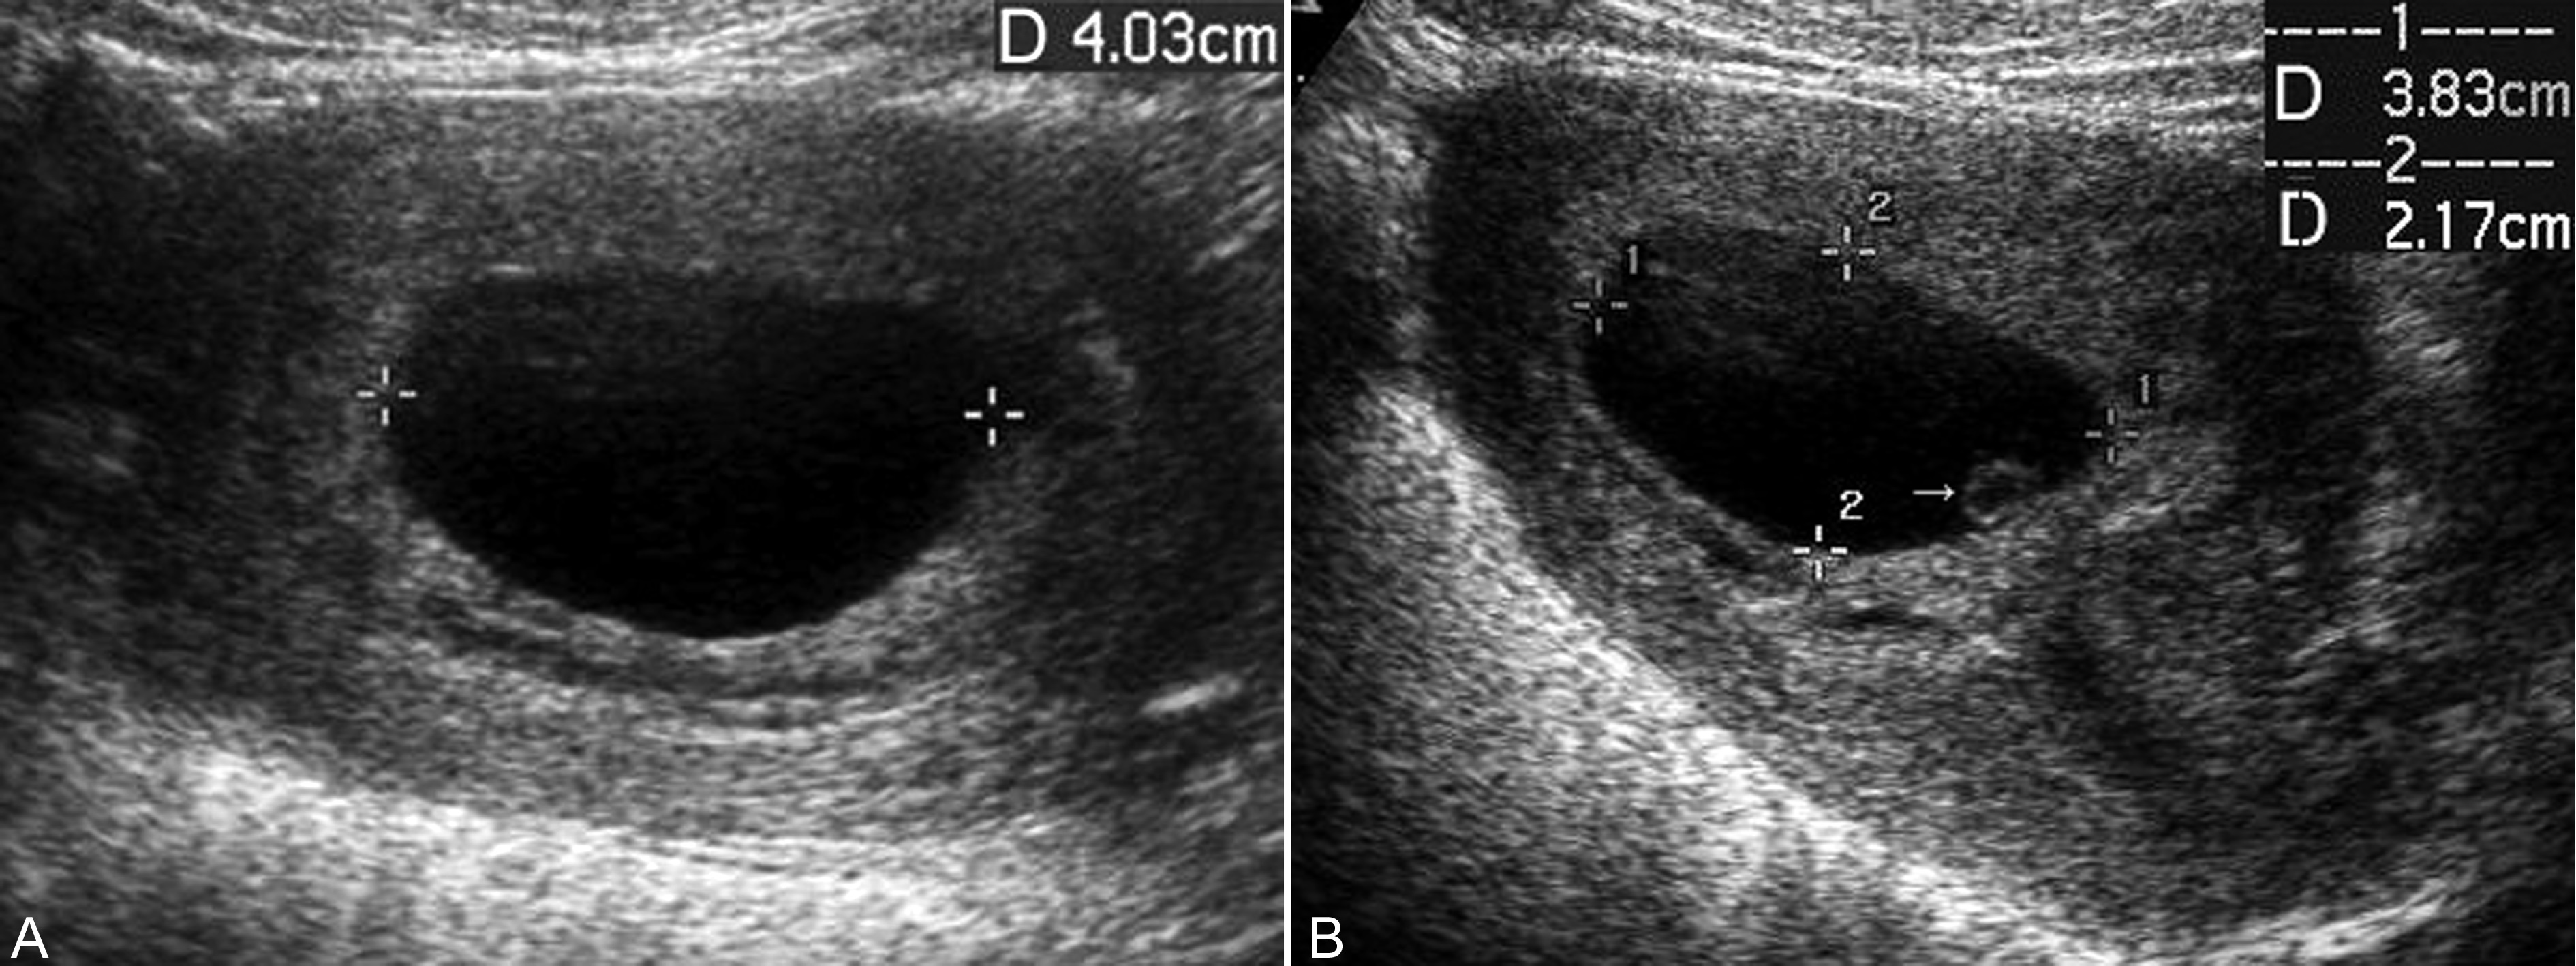

妊娠囊大小正常或较正常缩小,位置下移、变形(图3A)、边缘失去连续性;内部胚胎或胎儿活动消失,心脏搏动明显变弱或不规律、或消失(图3B);如果绒毛膜下血肿超过15ml以上并波及胎盘基底部,即便没有孕囊移位和胚胎死亡,多数也将以流产结束妊娠。

图3 难免流产声象图:变形的孕囊(GS)